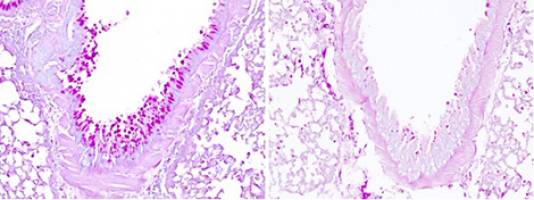

A team of Inserm and CNRS researchers from the Institute of Pharmacology and Structural Biology—or IPBS (CNRS / Université Toulouse III—Paul Sabatier)—have identified a protein that acts like a sensor detecting various allergens in the respiratory tract responsible for asthma attacks.